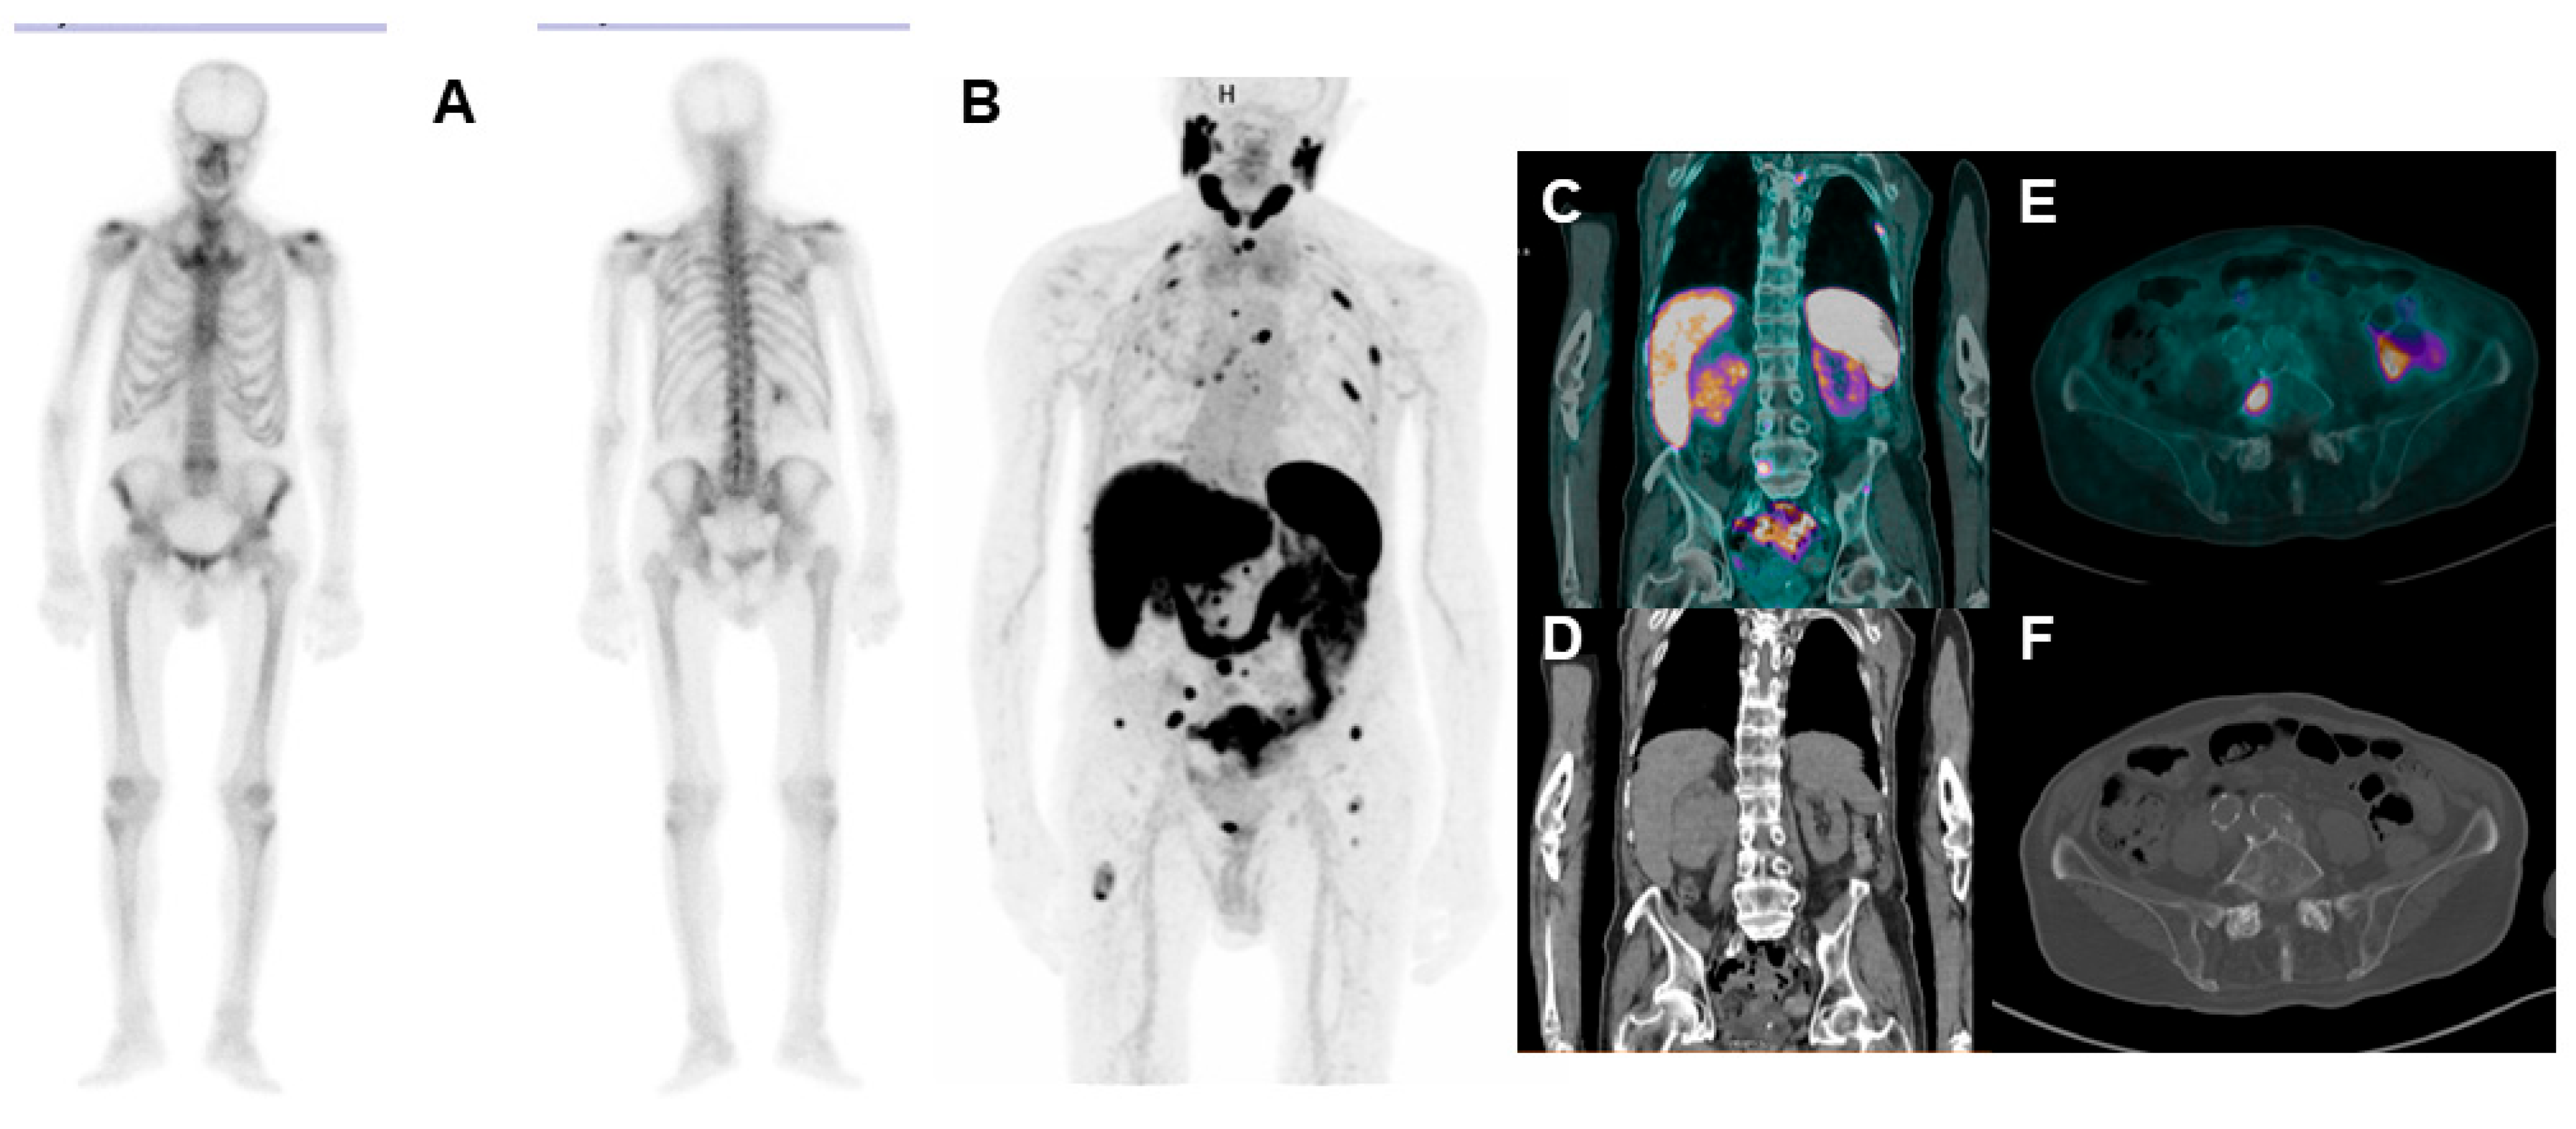

- Arnfield, E.G.; Thomas, P.A.; Roberts, M.J.; Pelecanos, A.M.; Ramsay, S.C.; Lin, C.Y.; Latter, M.J.; Garcia, P.L.; Pattison, D.A. Clinical insignificance of [18F]PSMA-1007 avid non-specific bone lesions: A retrospective evaluation. Eur. J. Nucl. Med. Mol. Imaging 2021, 48, 4495–4507. [Google Scholar] [CrossRef]

- Grünig, H.; Maurer, A.; Thali, Y.; Kovacs, Z.; Strobel, K.; Burger, I.A.; Müller, J. Focal unspecific bone uptake on [18F]-PSMA-1007 PET: A multicenter retrospective evaluation of the distribution, frequency, and quantitative parameters of a potential pitfall in prostate cancer imaging. Eur. J. Nucl. Med. Mol. Imaging 2021, 48, 4483–4494. [Google Scholar] [CrossRef]

- Ninatti, G.; Pini, C.; Gelardi, F.; Ghezzo, S.; Mapelli, P.; Picchio, M.; Antunovic, L.; Briganti, A.; Montorsi, F.; Landoni, C.; et al. The potential role of osteoporosis in unspecific [18F]PSMA-1007 bone uptake. Eur. J. Nucl. Med. Mol. Imaging 2023, 1–8. [Google Scholar] [CrossRef]

| Malignant Findings | UBU Findings |

|---|---|

| Sclerotic/blasting change at any follow-up imaging | PSA < 0.1 ng/mL after curative surgical treatment |

| SUVmax increase (e.g., ≥30%) on follow-up 18F-PSMA-1007 PET, independent from any treatments | Unchanged uptake on follow-up 18F-PSMA-1007 PET with or without therapy after >6 months |

| Treatment-related changes (e.g., reduction in size or increased sclerosis) on follow-up | No longer present on follow-up 18F-PSMA-1007 |

| Appearance of metastatic lesion on different imaging techniques (e.g., 68Ga-PSMA-11 PET, MRI, bone scan, CT) | Benign aspect on a different imaging modality |

| Association with typical symptoms of malignancy | Managed as likely benign after clinical evaluation |

| Association with blood biomarkers (i.e., PSA and ALP increasing/decreasing) | PSA stable or undetectable PSA |